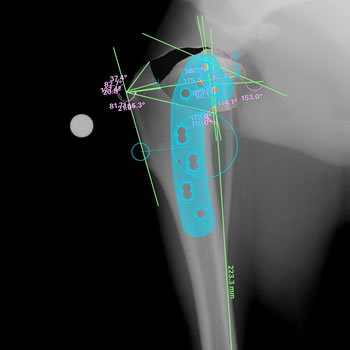

当院では、総合診療を基本としつつ、2009年より犬の膝疾患に特化した整形外科治療を開始しています。愛犬の前十字靭帯断裂や膝蓋骨脱臼(パテラ)などの膝疾患でお悩みの飼い主様、愛犬の歩き方が気になる飼い主様に、より良い整形外科をご提供できるよう専門の膝疾患チームを立ち上げています。現在、年間60〜80件の外科が必要な膝症例に向き合いながら、チームで日々の診療に励んでいます。